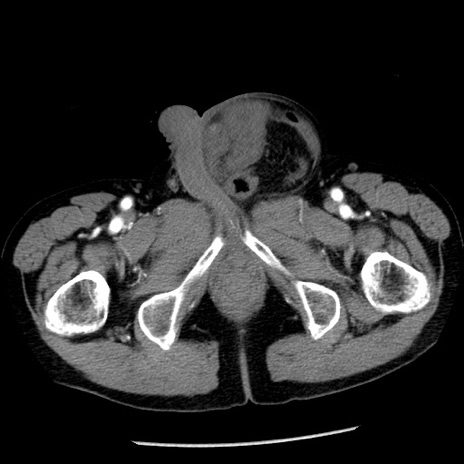

症例26(横断像)

【症例】80歳代男性

【主訴】嘔吐

【現病歴】昨晩2回嘔吐あり、今朝になっても嘔吐あり。来院。

【既往歴】胃潰瘍

【身体所見】意識清明、BT 37.6℃、BP 166/95mmHg、HR 100bpm、SpO2 97%、腹部:平坦・軟、腸蠕動音聴取良好、圧痛なし。

【データ】WBC 21900、CRP 1.46